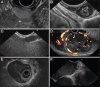

Endoscopic features of selected subepithelial lesions. (A) Gastric gastrointestinal stromal tumor with a central ulceration. (B) Inflammatory fibroid polyp with ulceration. (C) Lipoma in the transverse colon with a positive pillow sign after indentation with the closed biopsy forceps (arrow). (D) Lymphangioma with translucent appearance, the septated lesion appears lobulated on macroscopic inspection. (E) Pancreatic rest in the antrum with umbilication. (F) Granular cell tumor. A yellowish hue becomes particularly visible after superficial biopsy (small picture)

Endosonographic features of selected subepithelial lesions. (A) Hyperechoic gastric lipoma, arising from the 3rd endoscopic ultrasound layer (by courtesy of Prof. Dr. Uwe Will, Gera). (B) Small gastric leiomyoma with calcifications (atypical), arising from 4th hypoechoic layer. (C) Small gastric gastrointestinal stromal tumor (GIST), arising from 4th hypoechoic layer (arrowhead). (D) Large gastric GIST with distinct heterogeneity and small anechoic cavities (arrow heads), highly vascularized (contrast-enhanced power Doppler), arising from 4th hypoechoic layer. (E) Rare case of esophageal leiomyomatosis. The hypoechoic tumor nodules arise from the 4th hypoechoic layer. (F) Large esophageal leiomyoma arising from 4th hypoechoic layer